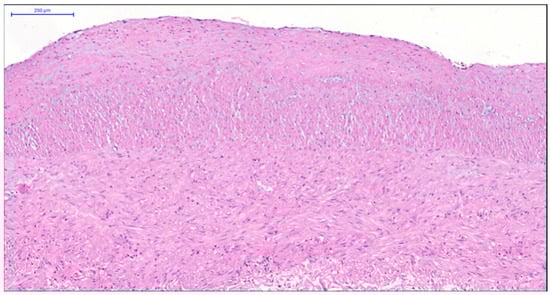

More pronounced structural alterations appear in the great saphenous vein of middle-aged and elderly individuals under normal conditions. Age-related changes manifest as uneven wall thickness and structural heterogeneity. Areas with thinner walls show reduced proportions of longitudinal and circular smooth muscle layers, while thicker regions contain these layers at maximal density (Figure 2 and Figure 3). The circular smooth muscle bundles become increasingly separated by connective tissue, creating a disorganized appearance.

Figure 2. Fragment of the great saphenous vein in individuals of the second age group. Hematoxylin and eosin staining. Magnification × 100. Segment of the vein with minimal and maximal wall thickness.